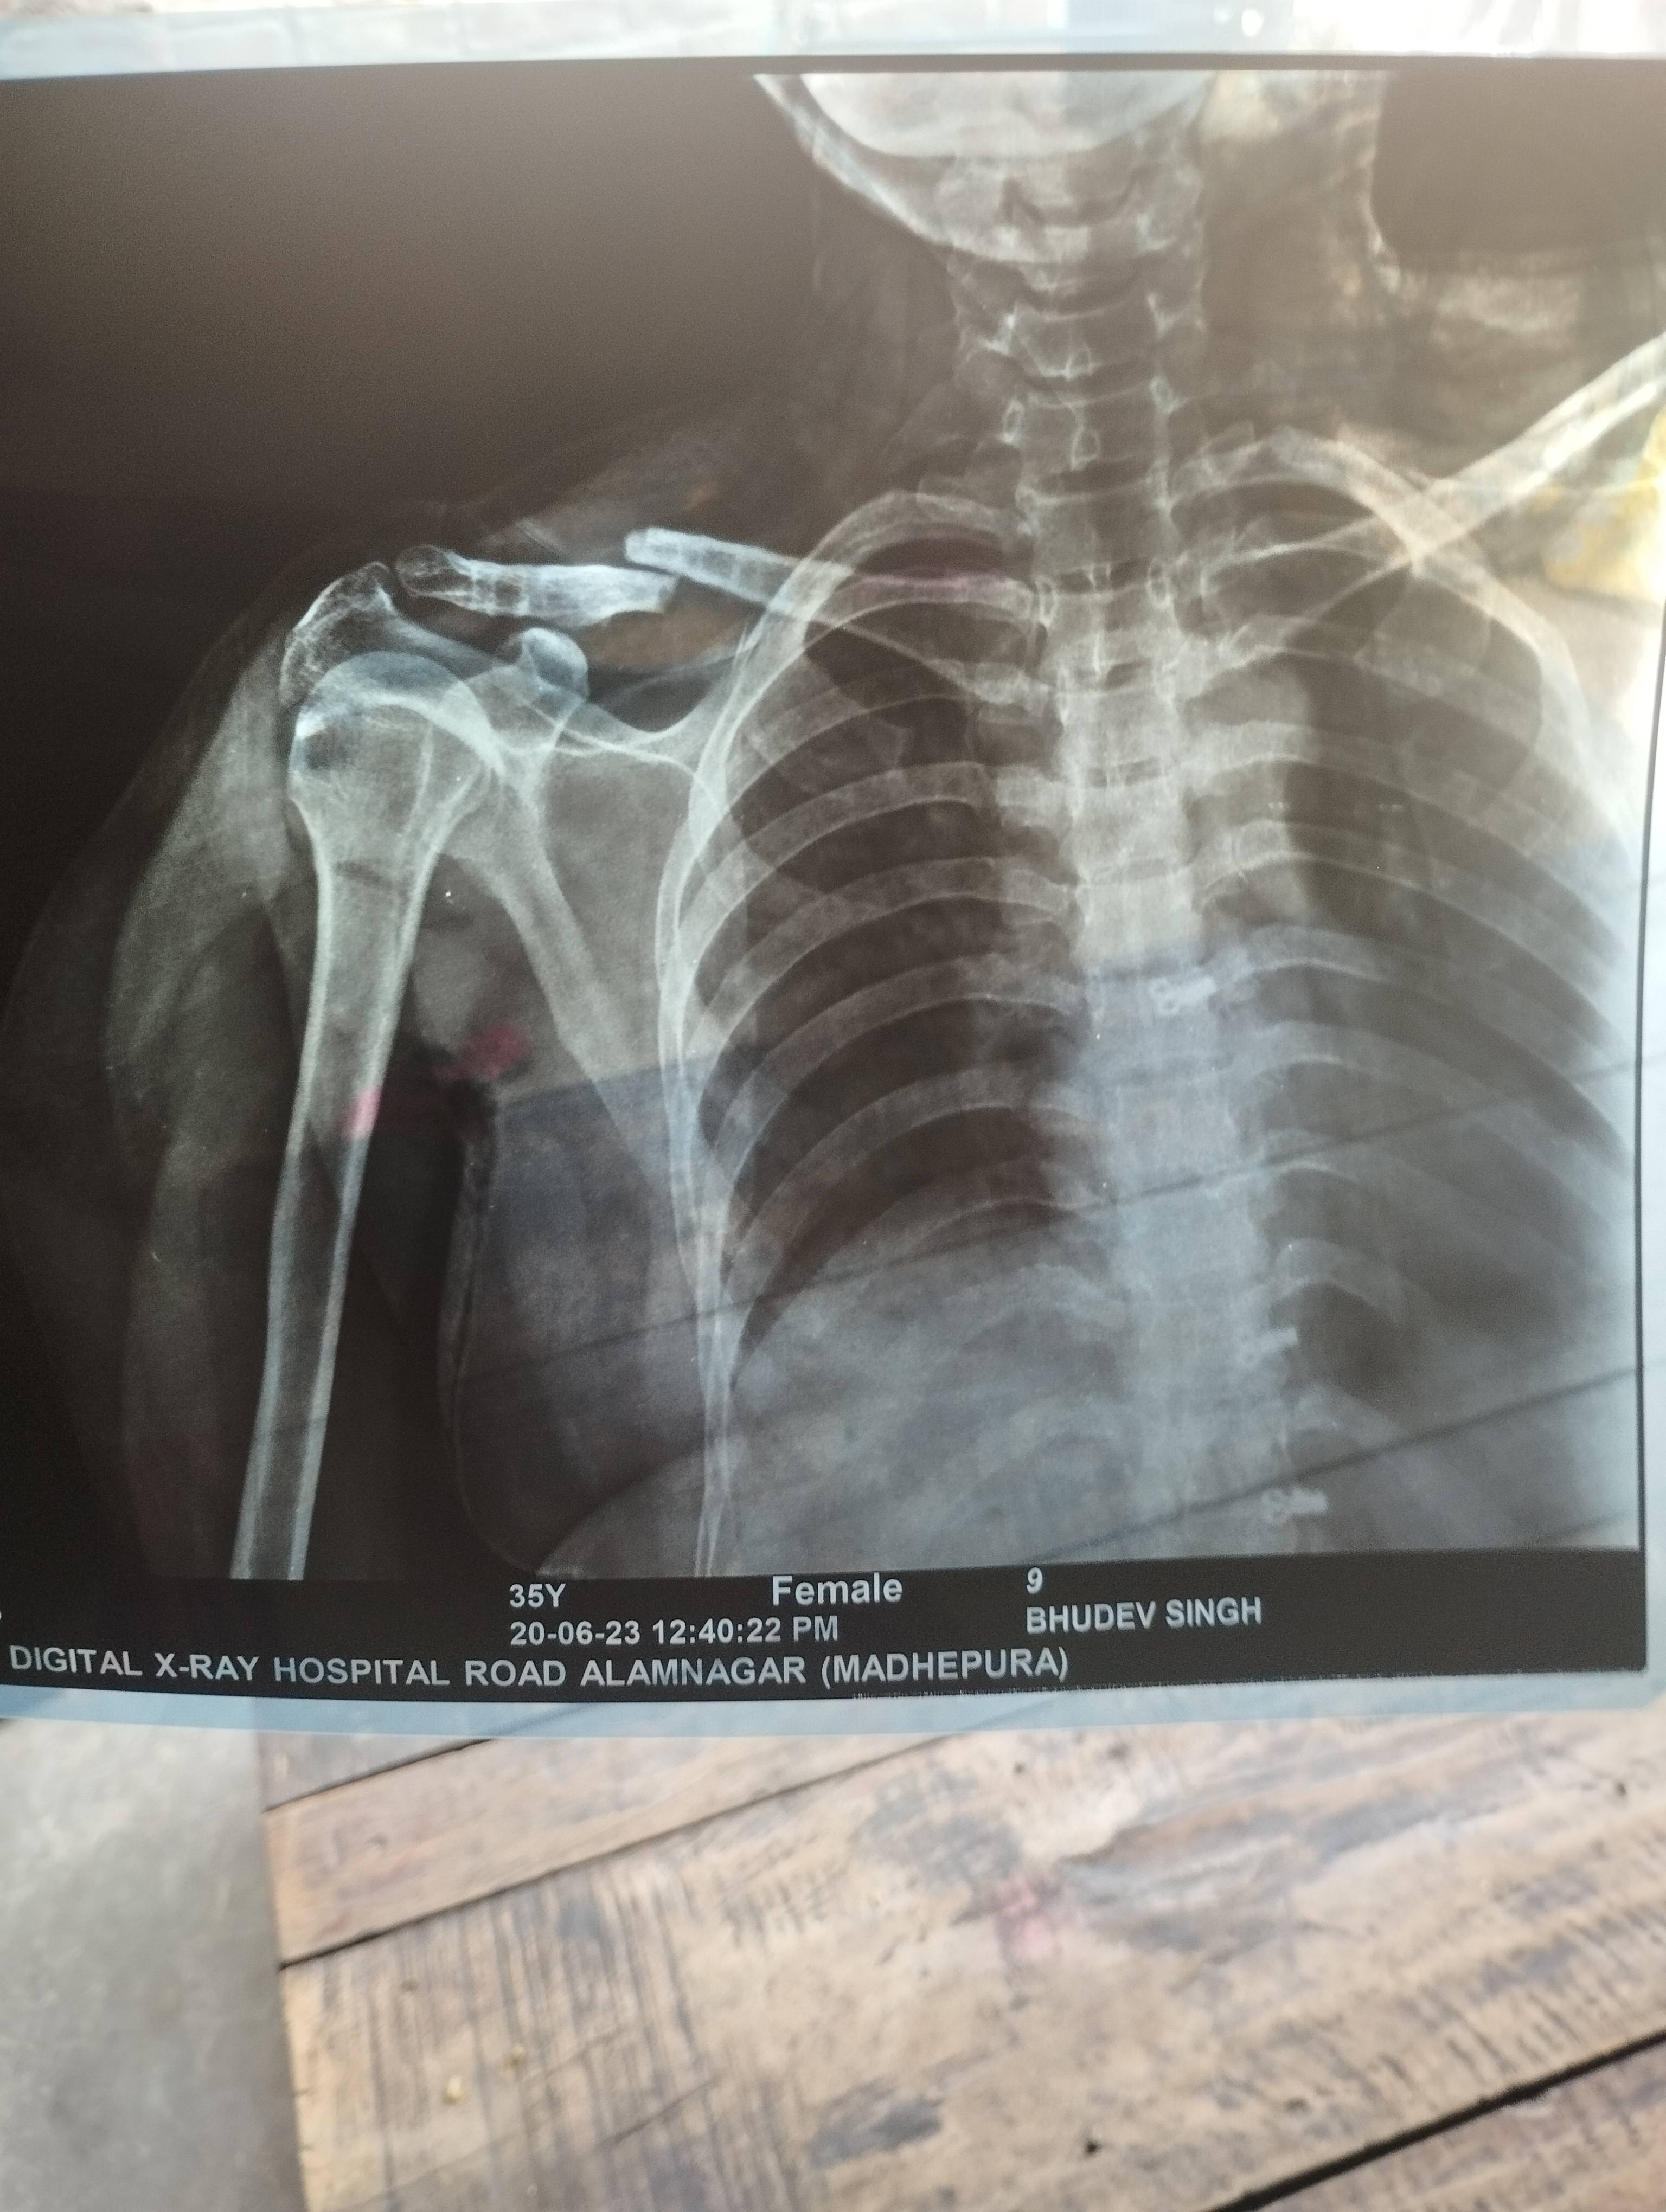

Sir i had got some fracture on hand and docs operate me on k-wire surgery on 14/06/23. Would you please suggest me for minimum how much time I'll remove those plaster and k wiring. As I have recently recruited for new job and I have to join it urgently